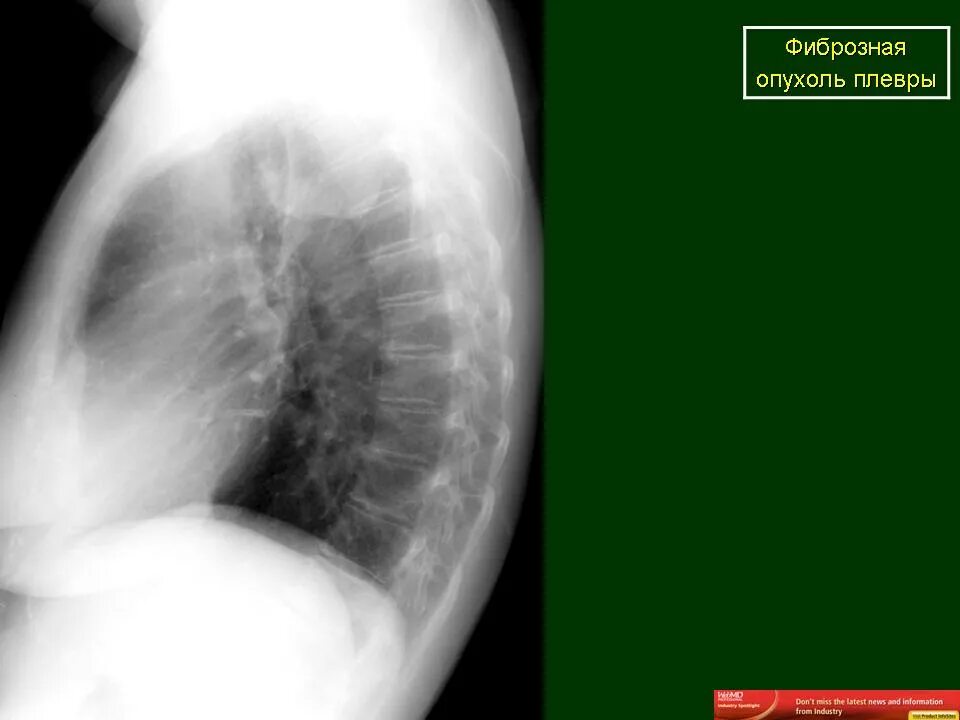

Метастазы плевры